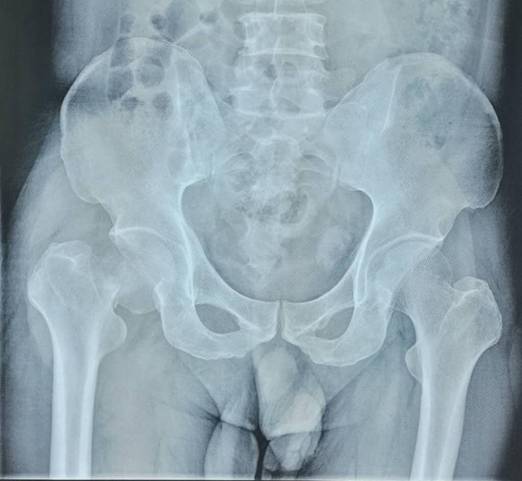

术前术后对比

全膝关节翻修术

全髋关节翻修术